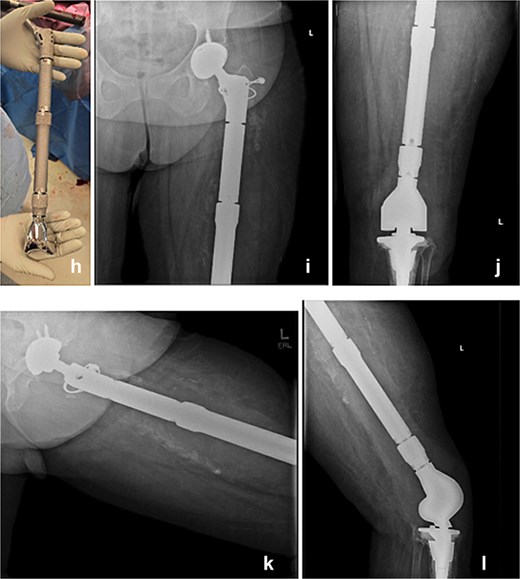

The modular TFR implant (h) is grossly visualized prior to implantation. Immediate postoperative anteroposterior (i and j) and lateral (k and l) radiograph following definitive reimplantation, showing the modular total femur replacement with a dual mobility acetabular component proximally and a rotating-hinge knee mechanism distally in appropriate alignment.

Seven days later, reimplantation was performed. A press-fit cup with a dual mobility liner was placed in the acetabulum to reduce dislocation risk. A modular TFR system was used: proximally, a femoral stem compatible with the dual mobility head; distally, a rotating-hinge knee mechanism attached to a tibial stem. Soft-tissue reconstruction was performed as feasible. The wound was closed over a drain and protected with a negative-pressure dressing. The patient remained non-weight-bearing with a knee immobilizer and continued intravenous cefazolin postoperatively for six weeks.

Stage two

Postoperatively, early imaging confirmed appropriate implant alignment. Motor function was preserved, and the incision healed without complication. She began a structured rehabilitation program with gradual progression to protected ambulation using an orthotic knee brace. At follow-up, the patient demonstrated functional limb

use, no signs of recurrent infection, and a stable prosthesis without evidence of hardware failure (Fig. 3).